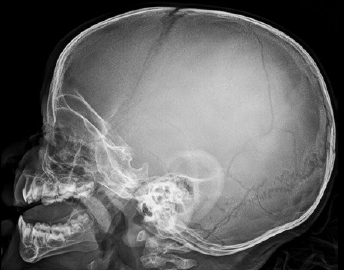

Q

TCE

¿Qué tipo de fractura es esta?

A

Fractura de base de cráneo